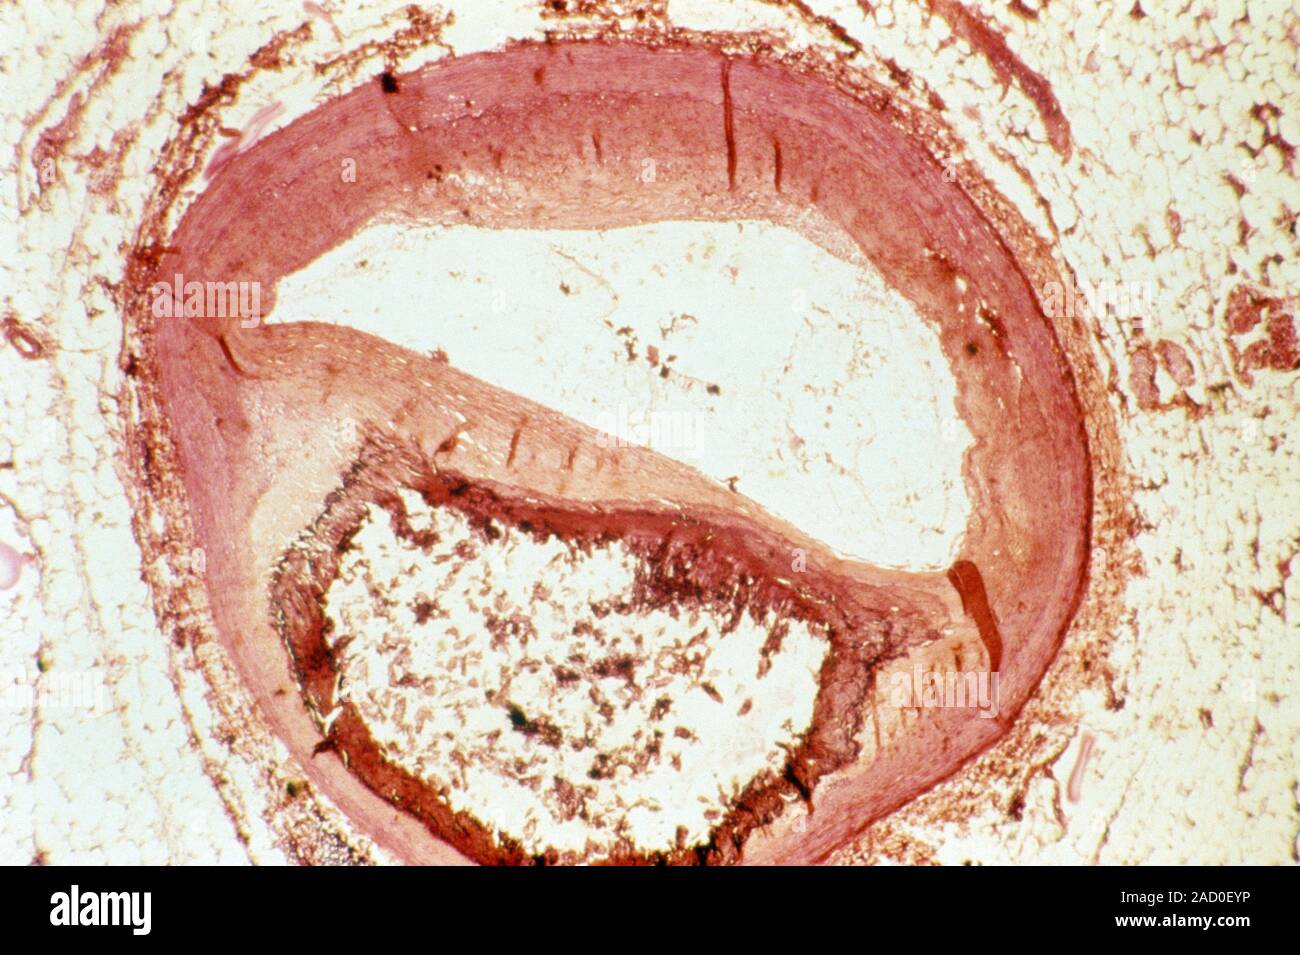

Атеросклеротическая бляшка аорты

Атеросклеротическая бляшка аорты 69 фотографий